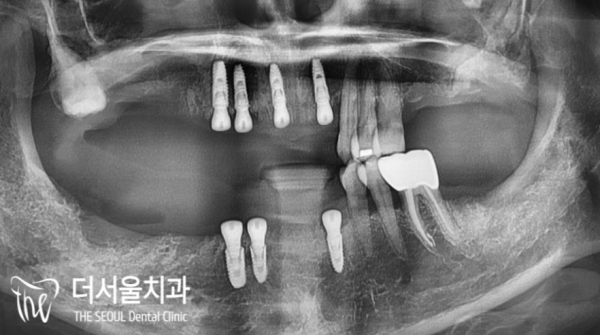

파노라마 사진을 촬영하여 보았더니 구치부의 치아는

대부분 상실되었고, 치조골 소실이 심각하게 나타나 있었습니다.

남아있는 치아들은 전체적으로 근심 방향을 향해 쏠려있기도 합니다.

전체적으로 살릴 수 있는 치아가 몇개 되지 않았으며

앞니 주변의 치아들이 흔들리고 있어서 급한 상황이었습니다.

I took a panoramic picture and found that the teeth in the detention center were

Most of them were lost, and alveolar bone loss was serious.

[Voiceover] The remaining teeth are generally directed towards the anxiety.

There are only a few teeth that can be saved

It was urgent because the teeth around the front teeth were shaking.

태평역치과 더서울치과에서 이 환자분의 치아에 임플란트를 심은

후이 파노라마 사진입니다.

Taepyeong Station Dental Clinic and The Seoul Dental Clinic planted implants in this patient's teeth

This is a panoramic picture of Hui.